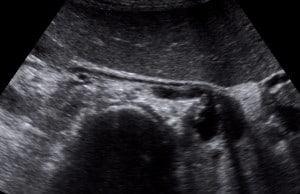

Explore a series of real-life renal Doppler case studies, focusing on the assessment of renal blood flow, diagnosis of renal artery stenosis, and management strategies. Learn how Doppler ultrasound can identify vascular abnormalities, optimize treatment plans, and improve patient outcomes in renal health.

Recognize the sonographic appearance of renal artery stenosis, renal vein thrombosis, pseudoaneurysm, and arteriovenous fistula.